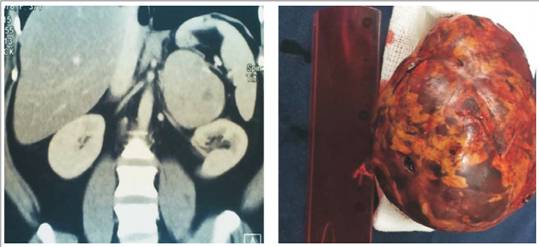

En todos los casos se trataba de lesiones unilaterales, con un tamaño promedio de 6 cm (rango 2-12 cm).(Figura 2)

El estudio anatomopatológico final de las lesiones resecadas determinó la presencia de nueve adenomas, cinco feocromocitomas, un mielolipoma y un hema toma.

En nuestra serie observamos resultados similares a los señalados en la bibliografía, con un buen rendimiento diagnóstico de la tomografía para determinar la naturaleza del IS, a excepción de dos casos: en uno, más allá de que la lesión superaba los 6 cm, no fue posible afirmar que se trataba de un adenoma por no presentar características típicas. En el otro caso (paciente hemofílico) la lesión, que tampoco tenía elementos distintivos, resultó ser un hematoma suprarrenal. El porcentaje de lesiones funcionantes es similar al referido en la literatura (19%), y la principal indicación de cirugía sigue siendo el tamaño y, en consecuencia, la necesidad de descartar malignidad. Asimismo, la mayoría de los IS corres pondía a adenomas no funcionantescorticosupra rrenales.